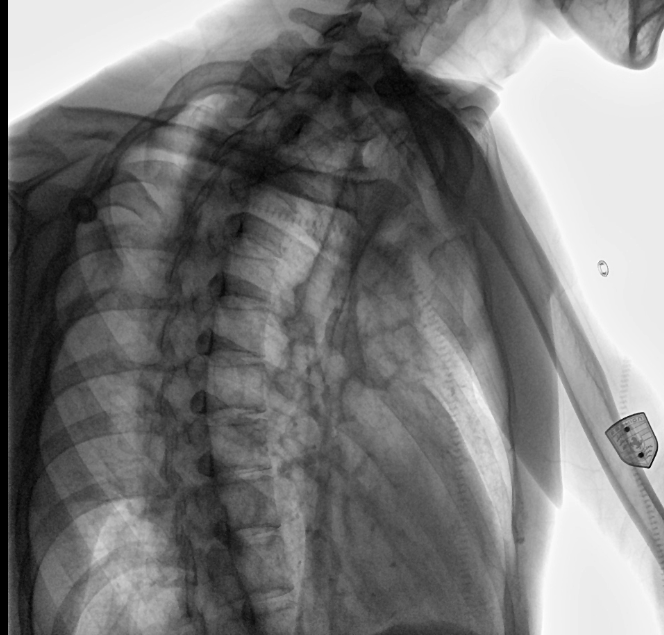

位于衡水市中醫(yī)醫(yī)院的動(dòng)態(tài)平板數(shù)字化X射線系統(tǒng)DTP571具備高速高清點(diǎn)片功能。這是一款對放射科十分友好的產(chǎn)品。因?yàn)樗迅咚俸透咔妩c(diǎn)片結(jié)合,既能方便影像技師有效地抓拍需要的病灶的影像,又能給予影像醫(yī)生清晰的影像進(jìn)行診斷。

動(dòng)態(tài)觀察診斷,實(shí)時(shí)高清點(diǎn)片